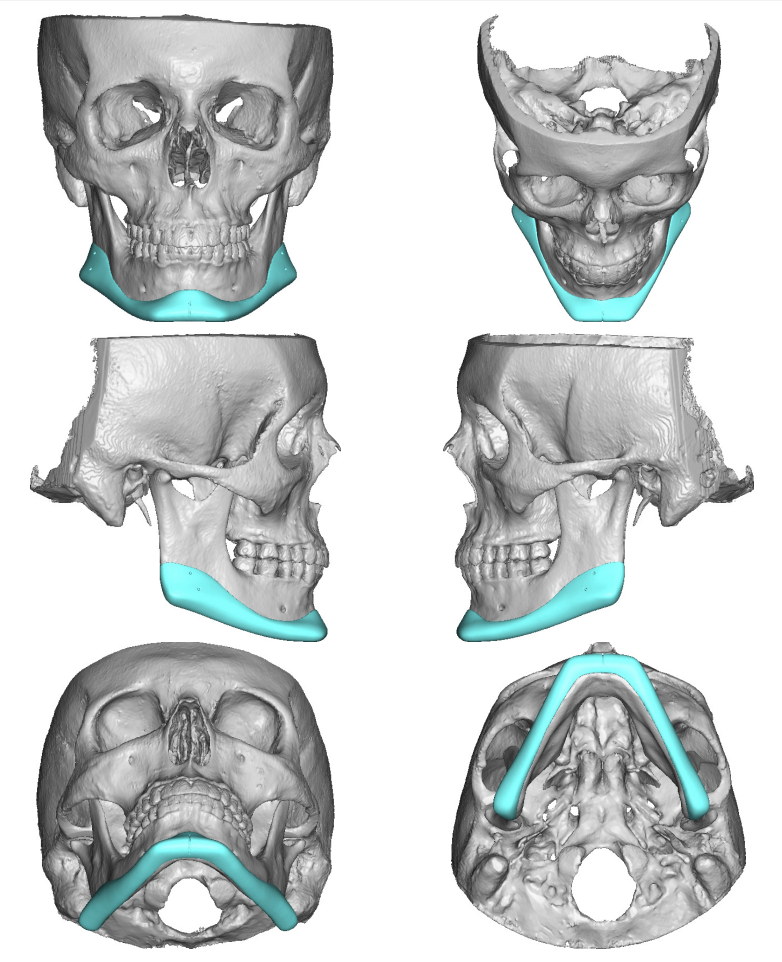

New implant notes:

-About 8mm right and 10mm left widening on jaws.

-Both sides of jaw about 4.5mm height added.

-Concavity to jaw shape added/fixed.

-Inframalars are 4.5mm and 5.5mm from 3/4 view.

-Fixed general asymmetries.

-3.1mm saddle.

-Infra rim shape has a slight, but improved, curve to keep a natural look.

New implant notes:

-About 8mm right and 10mm left widening on jaws.

-Both sides of jaw about 4.5mm height added.

-Concavity to jaw shape added/fixed.

-Inframalars are 4.5mm and 5.5mm from 3/4 view.

-Fixed general asymmetries.

-3.1mm saddle.

-Infra rim shape has a slight, but improved, curve to keep a natural look.